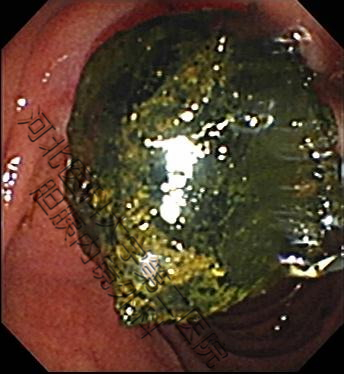

生活中并不缺少美,而是缺少发现美得眼睛,结石虽万恶,但具“自身美”,内镜下的结石也是“横看成岭侧成峰,奇形怪状各不同。簇拥颗粒如桑葚,表面圆滑似卵石。大如蜜枣小如豆,黑黄可见多半棕......”。接下来我们来一起欣赏百张内镜下取石的图片。(所见结石均已从胆总管取出,放入肠道内随大便排出)